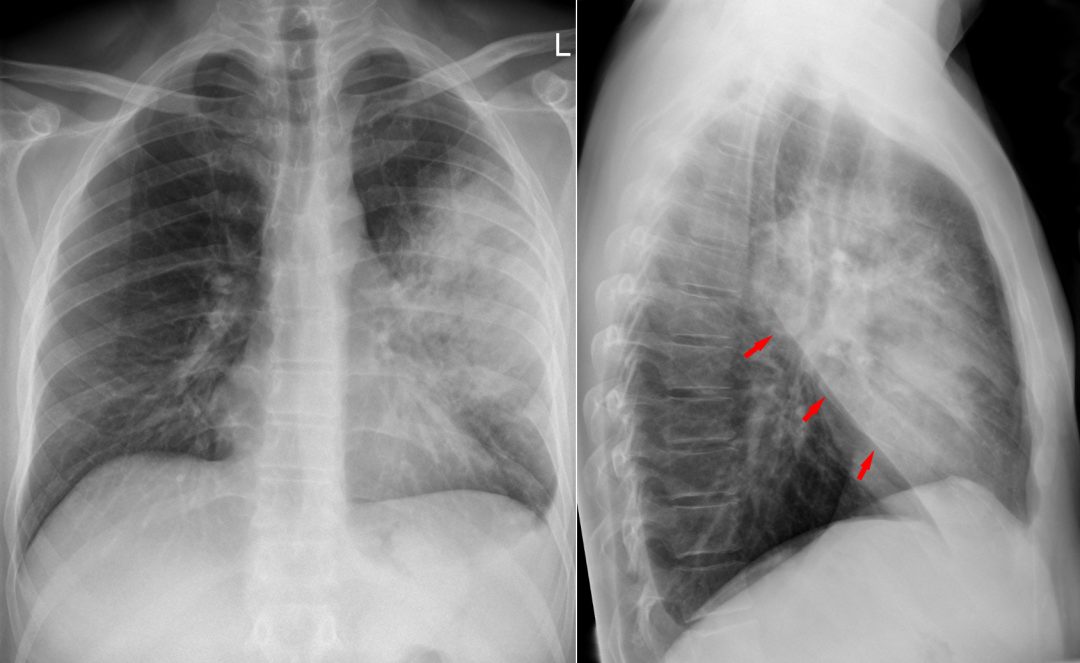

Per una corretta diagnosi è indicata l'esecuzione di una TAC ad alta risoluzione (HRTC). Una semplice radiografia del torace non è sufficiente e non fornisce abbastanza informazioni. Quadro tipico all'HRTC è la presenza di addensamenti alveolari migranti.